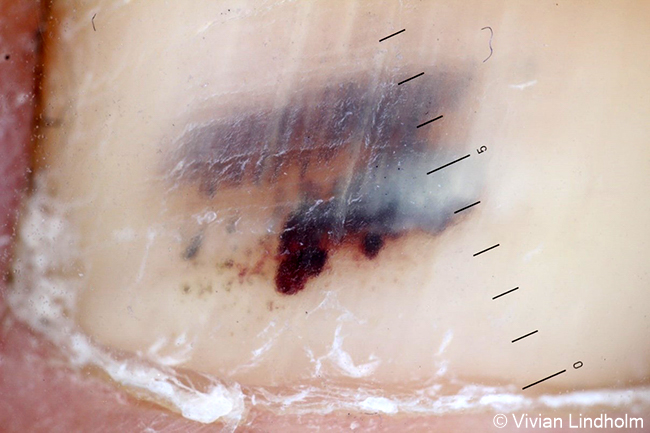

Subungual haematoma. Dermatoscopic image. Harmless haemorrhage underneath the nail. Large dark red globules (lagoons) can be seen in the image. The lesion is very probably benign as there is no pigmentation visible towards the nail base.

Image: Vivian Lindholm. Legend: Vivian Lindholm, Alexander Salava